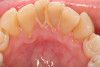

Răng khôn, hay còn gọi là răng số 8 (răng hàm thứ ba), là răng cuối cùng mọc lên trên hàm. Đôi khi, hàm có đủ chỗ để răng khôn có thể mọc lên khỏi lợi nhưng đa phần thì khả năng này không xảy ra. Thông thường, một trong những răng khôn này sẽ không thể mọc lên thẳng hàng hoặc không thể mọc lên hết khỏi lợi mà bị kẹt lại giữa xương hàm và lợi. Răng khôn không mọc hết có thể gây sưng, đau và nhiễm trùng vùng lợi ở quanh răng. Ngoài ra, răng không mọc hết có thể gây ra các tổn thương vĩnh viễn cho những răng, xương và phần lợi gần đó, thậm chí còn có thể dẫn đến sự hình thành mụn mủ và nhọt, phá hủy một phần hàm. Vì thế, các bác sĩ nha khoa thường khuyến khích việc phẫu thuật nhổ bỏ răng khôn.

Răng khôn không phải là loại răng duy nhất có thể mọc lệch và cần nhổ bỏ. Các loại răng khác, ví dụ như răng nanh và răng trước hàm cũng có thể mọc không hết và gây ra những ván đề tương tự nhue răng khôn.